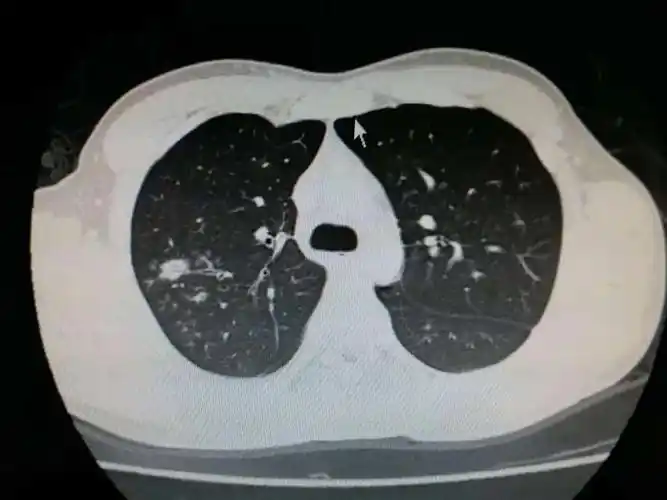

得了小儿病毒性肺炎怎么办-保健养生-在线问医生

这几组患儿胸片是肺炎还是正常影像规培医师懵了